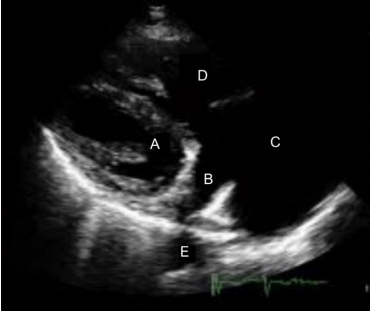

Na figura a seguir, identifique a estrutura representada em B.